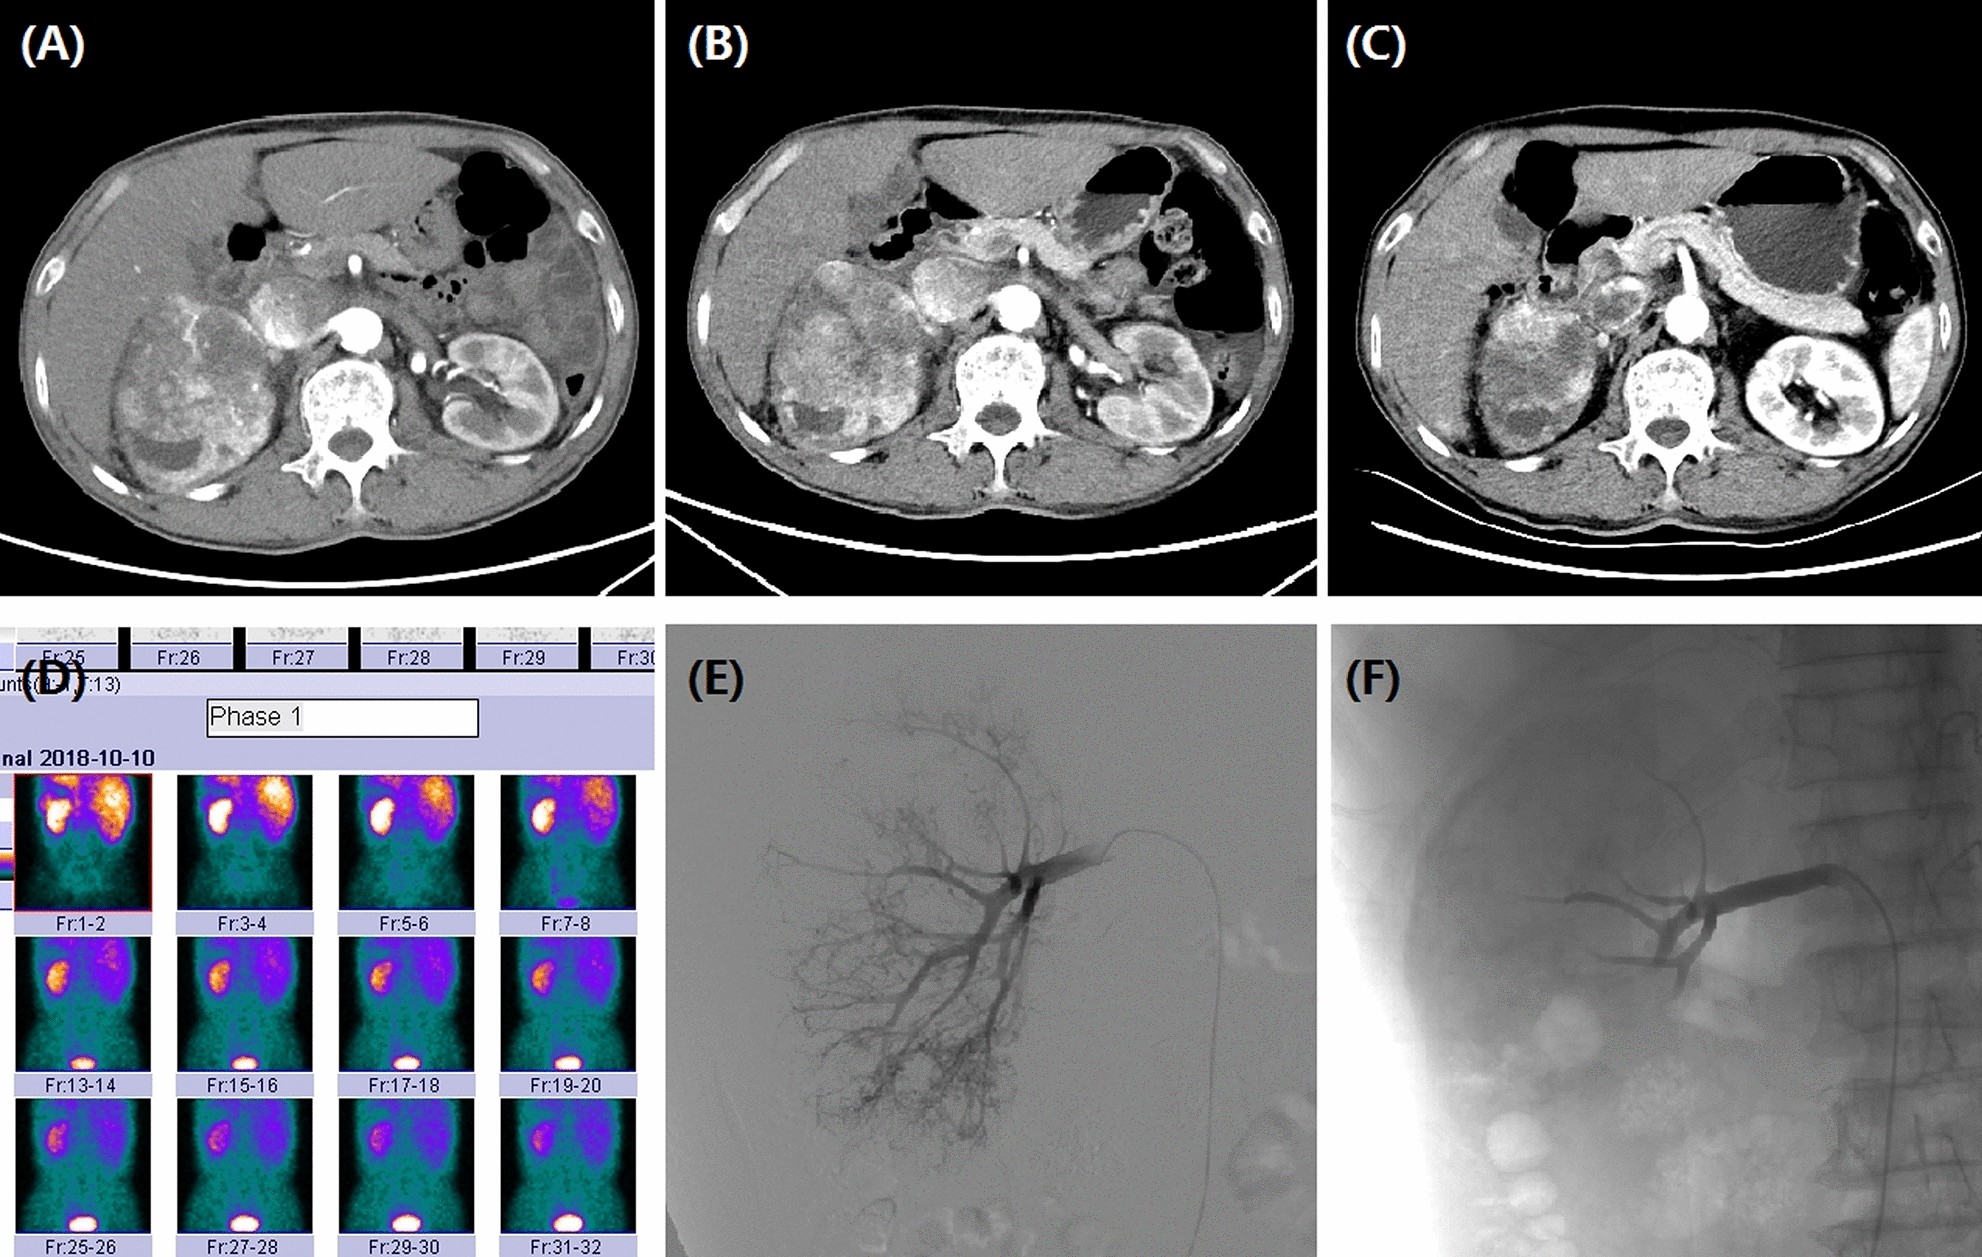

Figure 4

A 72-year male with right RCC treated by CB. (A) CT preoperative examination revealed a large tumor of the right kidney with tumor invasion into inferior vena cava. (B) The right renal tumor maintained stable after one month's follow-up. (C) The tumor shrunk at 3 months after DEB-TACE. (D) The right kidney showed a lower GFR (43.7 ml/min) than the left kidney (60.1 ml/min). (E) The right renal artery was the blood supply artery of the tumor. (F) The right renal artery was incubated and embolized.